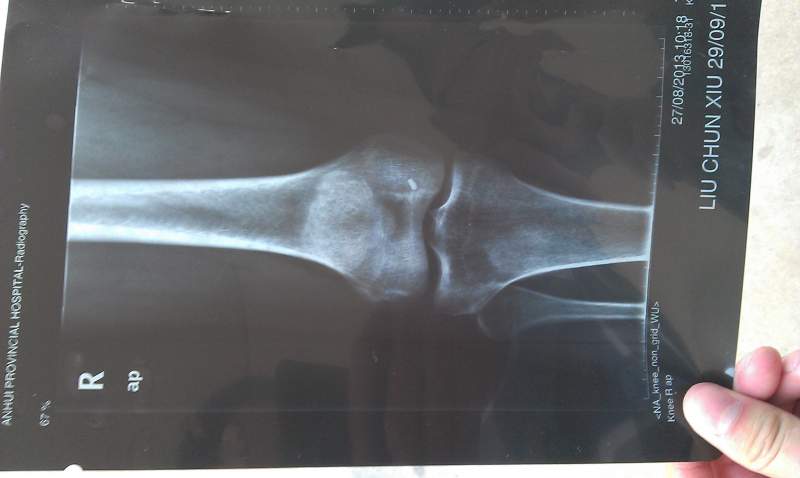

病情描述:膝盖内侧局部区域疼痛,只有那一小块地方,由于不小心崴的一下,已经有近两年时间,求助大神帮忙看下这个X光片,是个什么情况?X光片上规则白点是什么原因?是引起病症的直接原因吗? IMAG0062.jpg IMAG0063.jpg IMAG0064.jpg IMAG0065.jpg |